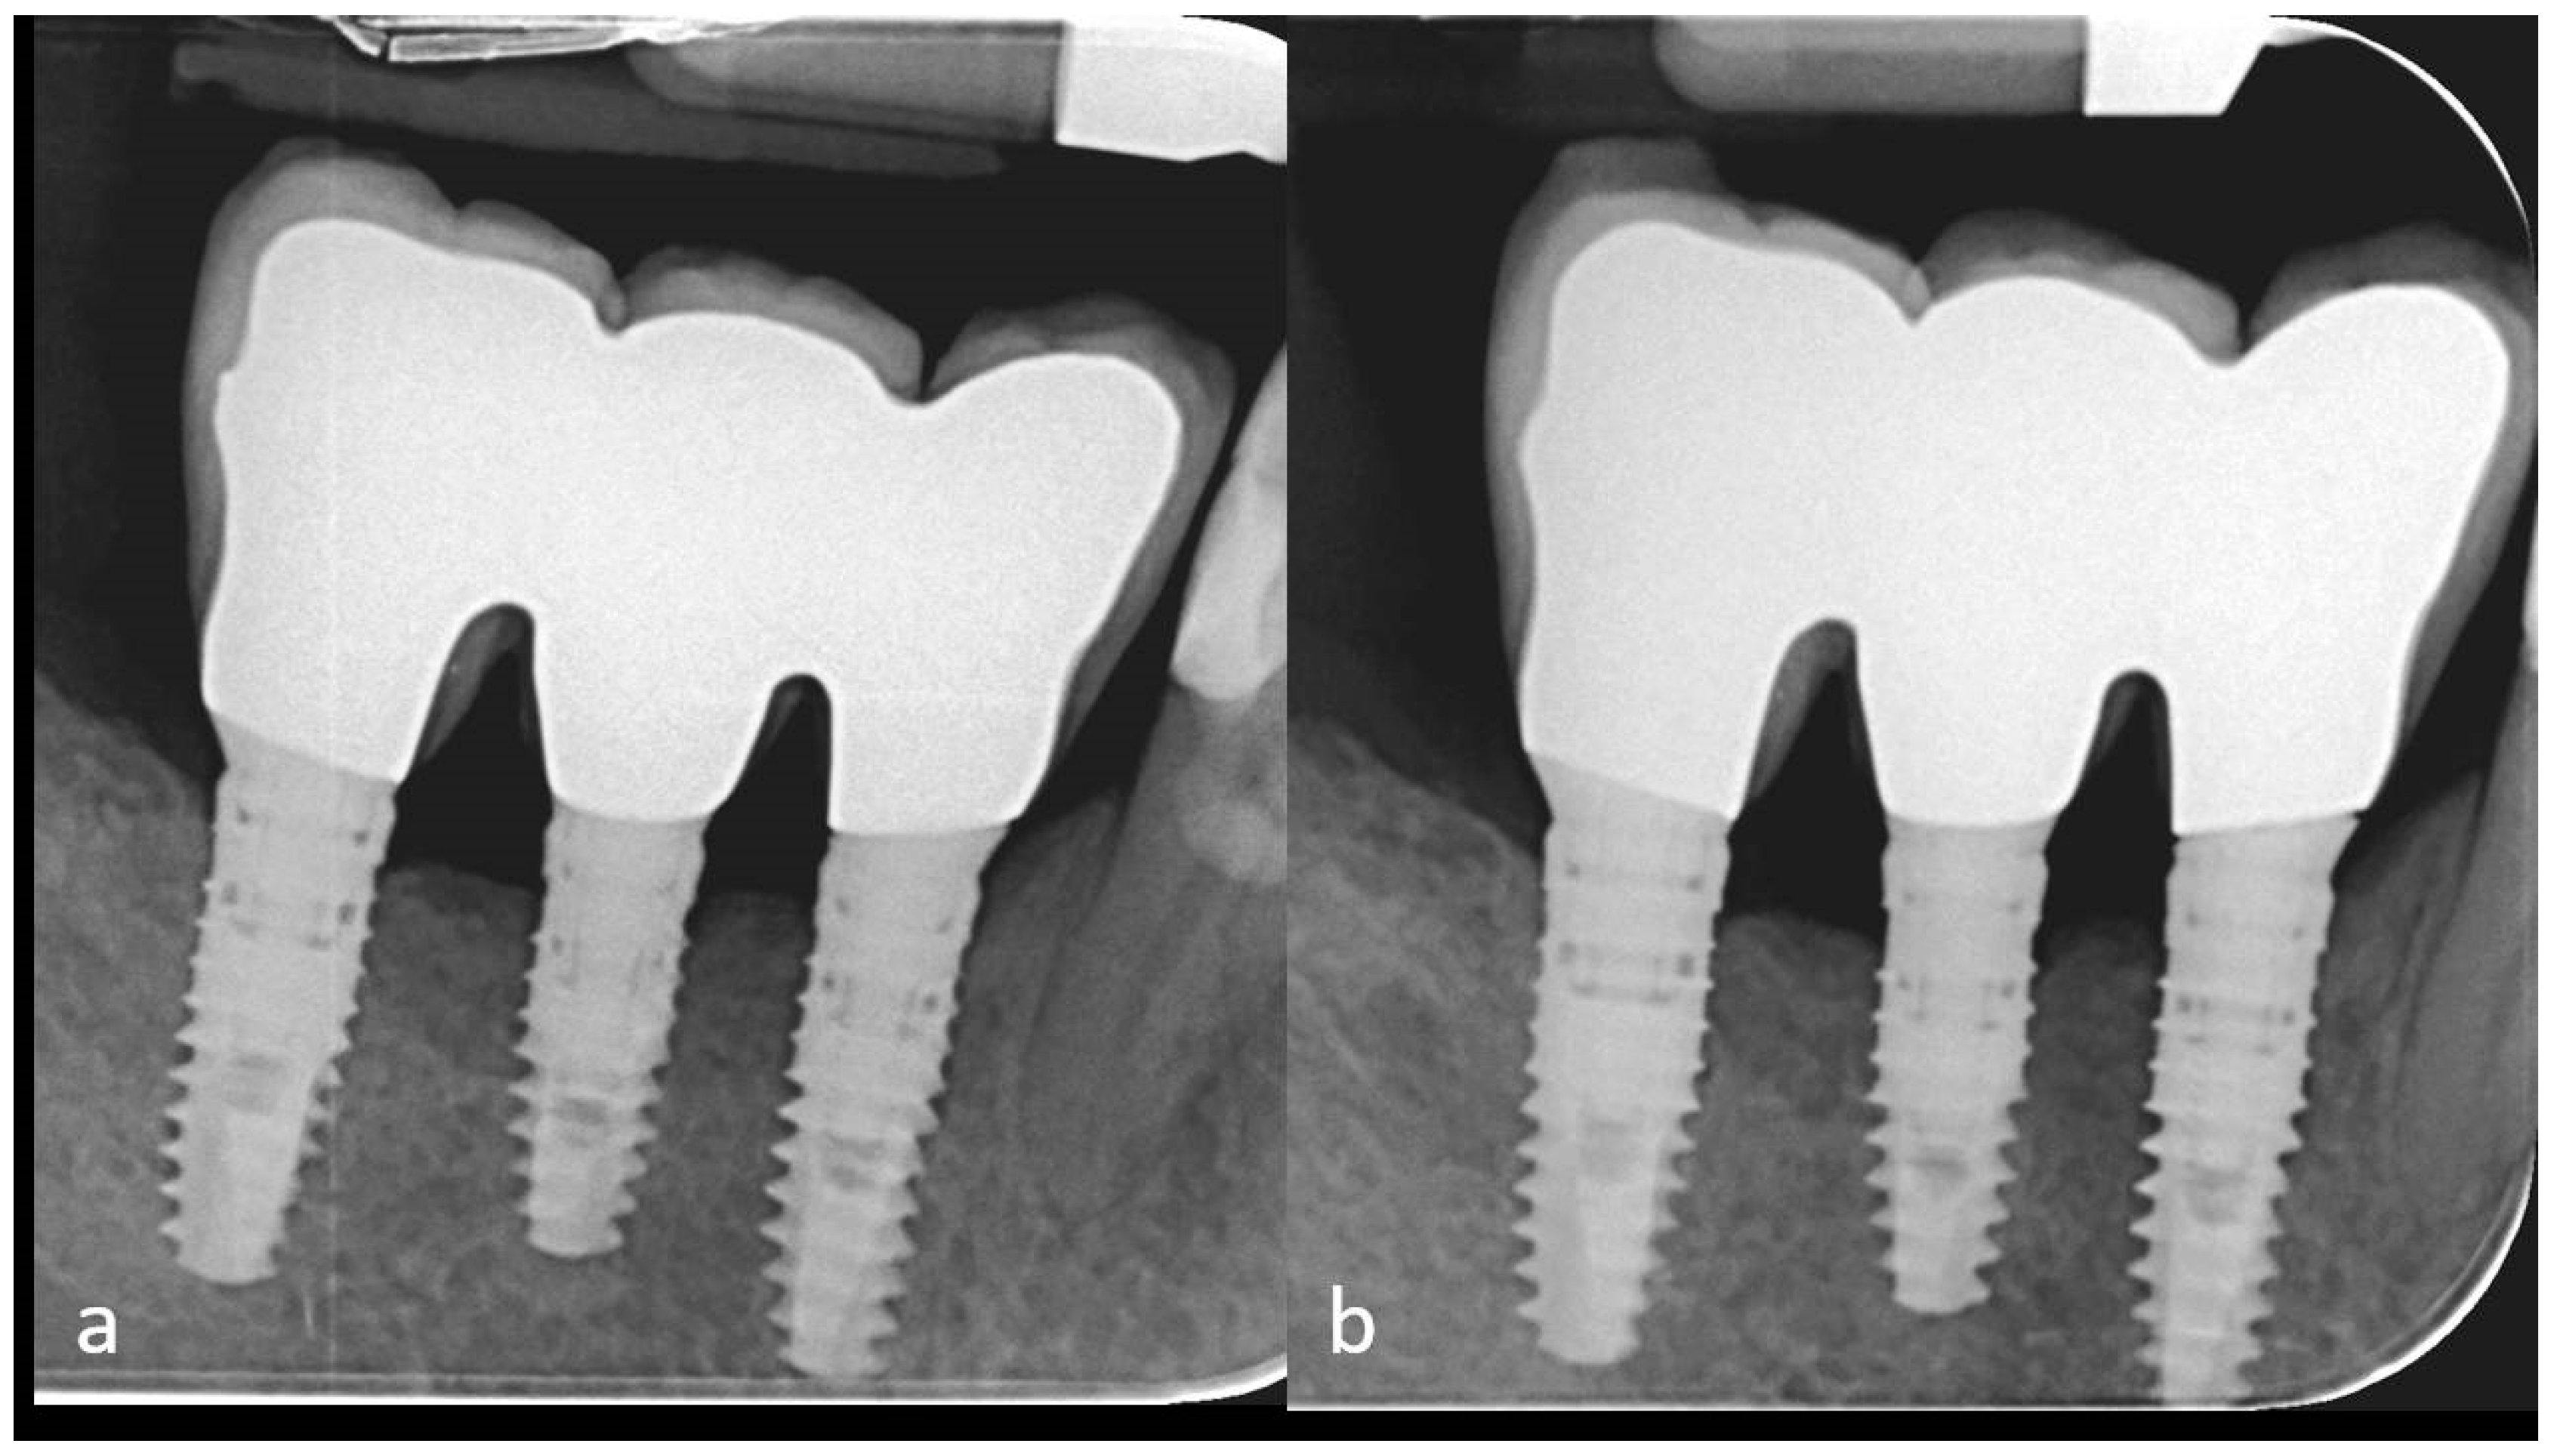

2. Case Description